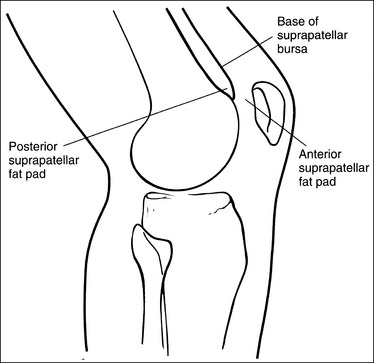

Contrast and density are adequate to demonstrate the suprapatellar fat pads.

• Suprapatellar fat pads. Two soft tissue structures of interest at the knee are used to diagnose joint effusion and knee injury. They are the posterior and anterior suprapatellar fat pads. Both are located anterior to the patellar surface of the distal femur and are separated by the suprapatellar bursa (Figure 6-82). Fluid that collects in the suprapatellar bursa causes the anterior and posterior suprapatellar fat pads to separate. It is a widening of this space that indicates a diagnosis of joint effusion.

The patella is situated proximal to the patellar surface of the femur, and the patellofemoral joint is open.

• The knee should be flexed 10 to 15 degrees. With less than 20 degrees of knee flexion, the patella is situated proximal to the patellar surface of the femur, the quadriceps are relaxed, and the patella is fairly mobile. In this patellar position the anterior and posterior suprapatellar fat pads can be easily used to evaluate knee joint effusion. Conversely, when the knee is flexed 20 degrees or more, a tightening of the surrounding knee muscles and tendons is present, the patella comes into contact with the patellar surface of the femur, and the anterior and posterior suprapatellar fat pads are obscured, eliminating their usefulness in diagnosing joint effusion (see Image 67). Some authors indicate that 20 to 30 degrees of knee flexion should be used on a lateral knee projection. Facility routines dictate the actual number of degrees that should be used.